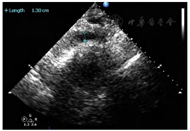

患者,女性,84岁,因"反复胸痛1周,持续加重8 h"于2021年8月17日急诊收治入院。既往无高血压、糖尿病病史。入院查体:血压105/56 mmHg(1 mmHg=0.133 kPa),神清,气略促,对答切题,颈软,颈静脉无怒张,双肺呼吸音粗可闻及较多的湿啰音,心率112次/min,律齐,各瓣膜区未闻及病理性杂音,腹平软,无压痛,反跳痛,肝脾肋下未及。双下肢轻度浮肿,四肢肌力正常,病理征(-);急诊心电图示:急性广泛前壁心肌梗死(图1);胸部CT提示双侧间质性肺水肿可能(图2);实验室检查:肌钙蛋白T:3.13 μg/L,肌酸激酶同工酶:188.93 μg/L,D二聚体:1.36 mg/L。根据患者病史、心电图及心肌酶学明确诊断为急性ST抬高型心肌梗死,予以术前嚼服负荷量绿色通道行急诊再灌注治疗,冠脉造影示:前降支次全闭塞,远端TIMI血流0级,回旋支近端40%~50%局限性狭窄,TIMI血流3级,右冠起源左冠窦,无狭窄,TIMI血流3级,于前降支近端植入3.0 mm×18 mm Firebird 2支架一枚(附件冠脉造影+PCI图3、视频1)后安返CCU。继续予以心电及血流动力学监测,动态监测心电图及酶学改变,阿司匹林、替格瑞洛抗血小板聚集,他汀调脂、稳定斑块,扩管利尿改善心功能等治疗。3 h后患者突发血压下降为60/40 mmHg,四肢湿冷,动脉搏动弱,意识尚清,指末氧饱和度95%,心电监测提示窦性心动过速,心率130次/min。立即予以平衡液扩容,多巴胺+去甲肾上腺素提升血压,留置颈内静脉置管监测CVP,股动脉置管监测有创动脉压。床旁心超提示微量心包积液,右房室内径偏小(37 mm×18 mm,40 mm×22 mm),左室壁多壁段运动异常,EF35%(图4),床位医师考虑容量不足,继续补液扩容及血管活性药物升压,但患者血压仍未见回升;再次复查心超提示心包积液较前明显增多,未见室壁不连续及异常血流信号,考虑心包填塞(图5),立即行心超定位剑突下心包穿刺,引流出暗红色不凝血,予以心包置管留置引流出血性液体300 ml,患者血压恢复至119/49 mmHg,心率95次/min,再次复查心超示左室心尖处见几束细丝状异常血流信号局限于纤维膜状回声内,考虑左室心尖破裂伴假性室壁瘤可能性大(图6)

术后患者突发血压下降为60/40 mmHg、四肢厥冷,床边心超提示心包积液进行性增加,心包穿刺及引流为暗红色不凝血300ml后,血压恢复正常,故急性心包填塞诊断明确;术中发现左室心尖部游离壁黑色血凝块附着,清除血凝块后多处散点状破裂出血,证实为心脏游离壁破裂(视频2)。

2.心超证实心包积液进行性增加,结合患者临床表现为突发血压下降、窦速、休克的表现,考虑急性心包压塞,有心包穿刺引流的指证,解除急性心包压塞同时也可明确心包积液的性质有助于诊断;经心包穿刺引流后,患者迅速血压回升,血流动力学稳定,并且心包积液为暗红色不凝血,高度提示心脏破裂,复查心超左室心尖处见几束细丝状异常血流信号,局限于纤维膜状回声内,考虑左室心尖破裂伴假性室壁瘤可能性大,根据病史及辅助检查诊断明确,请心外科会诊有急诊手术指征,心外科予以急诊开胸探查,术中见心尖呈花斑样改变,心尖黑色血凝块附着,可见多处散点状破裂出血,手术诊断为左心室破裂,予以自身心包补片5 cm×5 cm,填充速即纱、猪源生物胶修补,术后安返ICU进一步治疗。